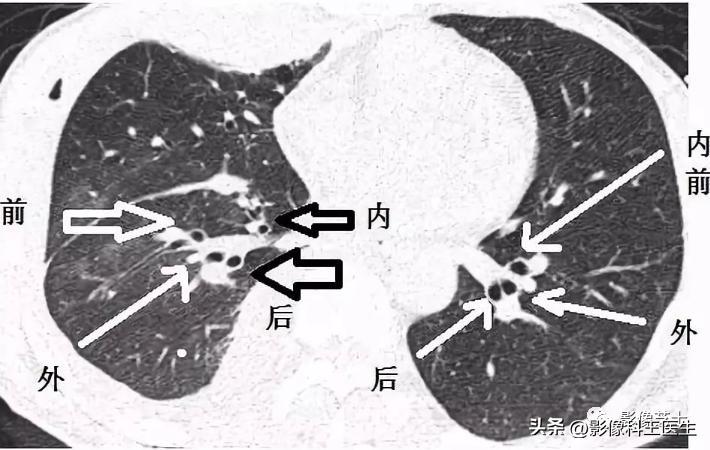

肺段、支气管分段CT解剖(详细标注)

肺部解剖分叶分段CT

二、右肺

又短又粗,走行陡峭

肺的分段